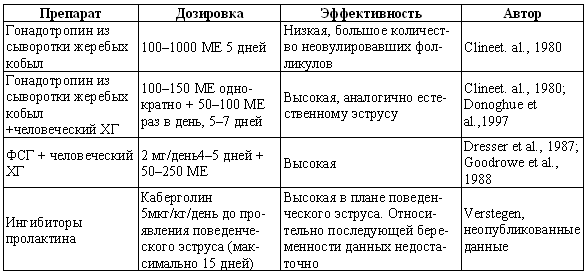

Фиг. 2.2.

Вагинальные выделения кошки (а). Выделения, типичные для фазы эструса. Большая часть клеток представляет собой безъядерные кератинизированные клетки или клетки с пикнотическим ядром. Присутствуют промежуточные клетки (b). Выделения, характерные для метэструса, — «течки», иногда наблюдаемой у кошек в конце эструса. Присутствуют поверхностные и промежуточные клетки, повышено содержание лейкоцитов. Этот короткий метэструс наблюдается в течение 24–48 часов (см. Приложение)